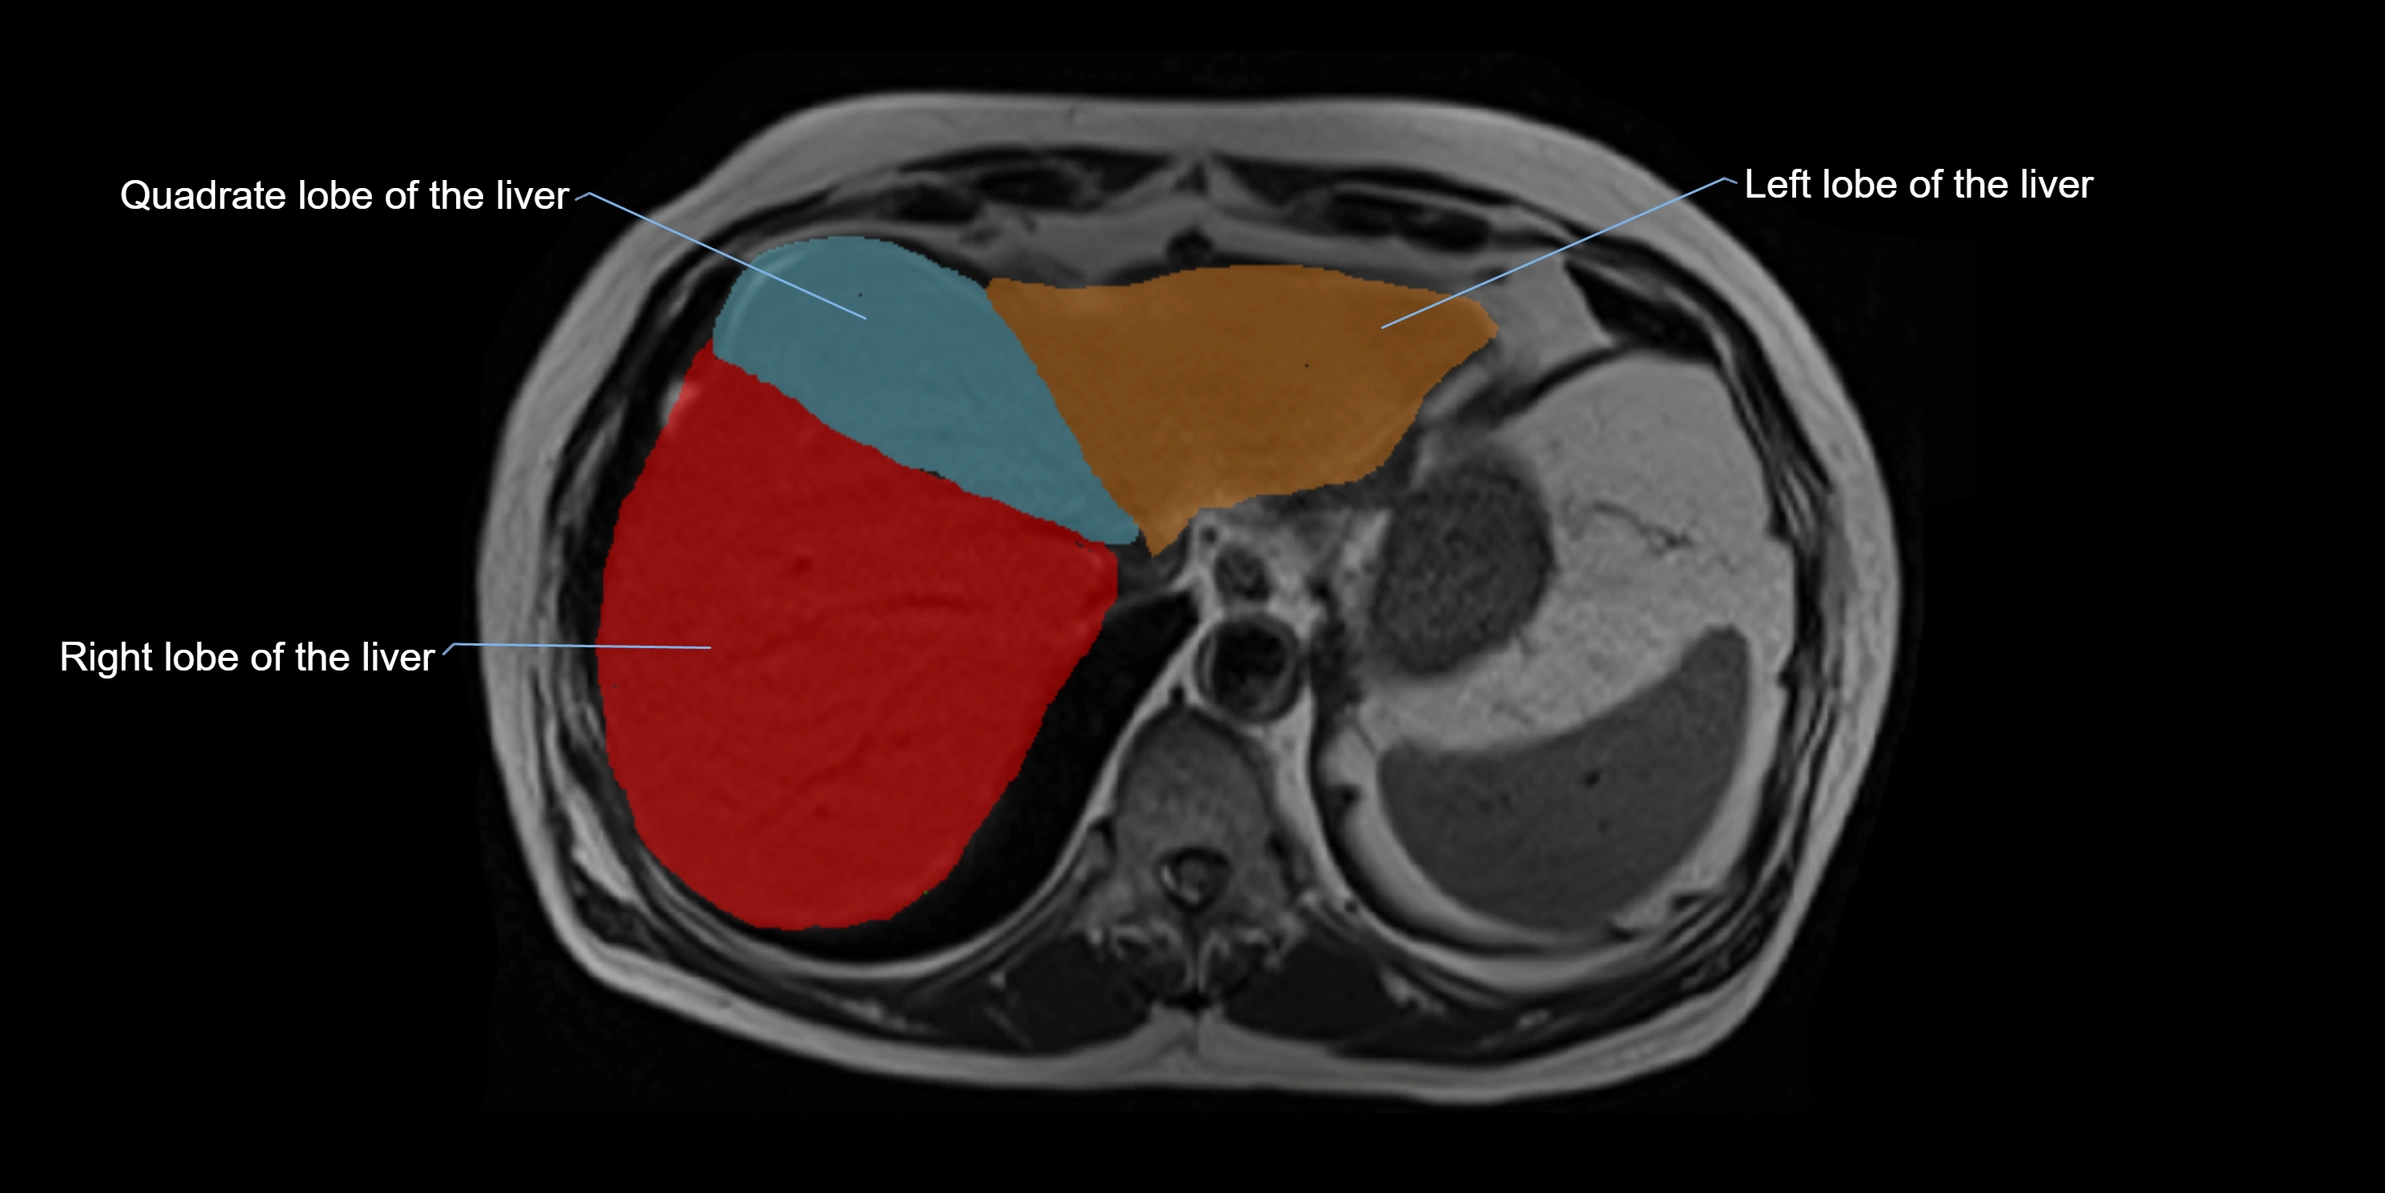

The caudate lobe of the liver is a distinct anatomical subdivision of the liver, designated as segment I in Couinaud’s classification. It lies on the posterior surface of the liver, between the fissure for the ligamentum venosum (left boundary) and the groove for the inferior vena cava (IVC) (right boundary). Superiorly, it is related to the posterior liver surface, and inferiorly it is separated from the left lobe by the porta hepatis.